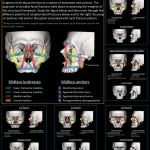

- Acute right zygomaticomaxillary complex fracture with nondisplaced fracture of the zygomatic arch, mildly displaced fractures of the zygomatic and frontal bones near the zygomaticofrontal suture, mildly displaced fractures of the lateral and inferior orbital walls, and mildly displaced fractures of the anterior, posterior, and medial walls of the maxillary sinus. The orbital floor fracture involves the infraorbital foramen

- ZMC fracture

Acute right zygomaticomaxillary complex (ZMC) fracture with nondisplaced fracture of the zygomatic arch, mildly displaced fractures of the zygomatic and frontal bones near the zygomaticofrontal suture, mildly displaced fractures of the lateral and inferior orbital walls, and mildly displaced fractures of the anterior, posterior, and medial walls of the maxillary sinus. The orbital floor fracture involves the infraorbital foramen.